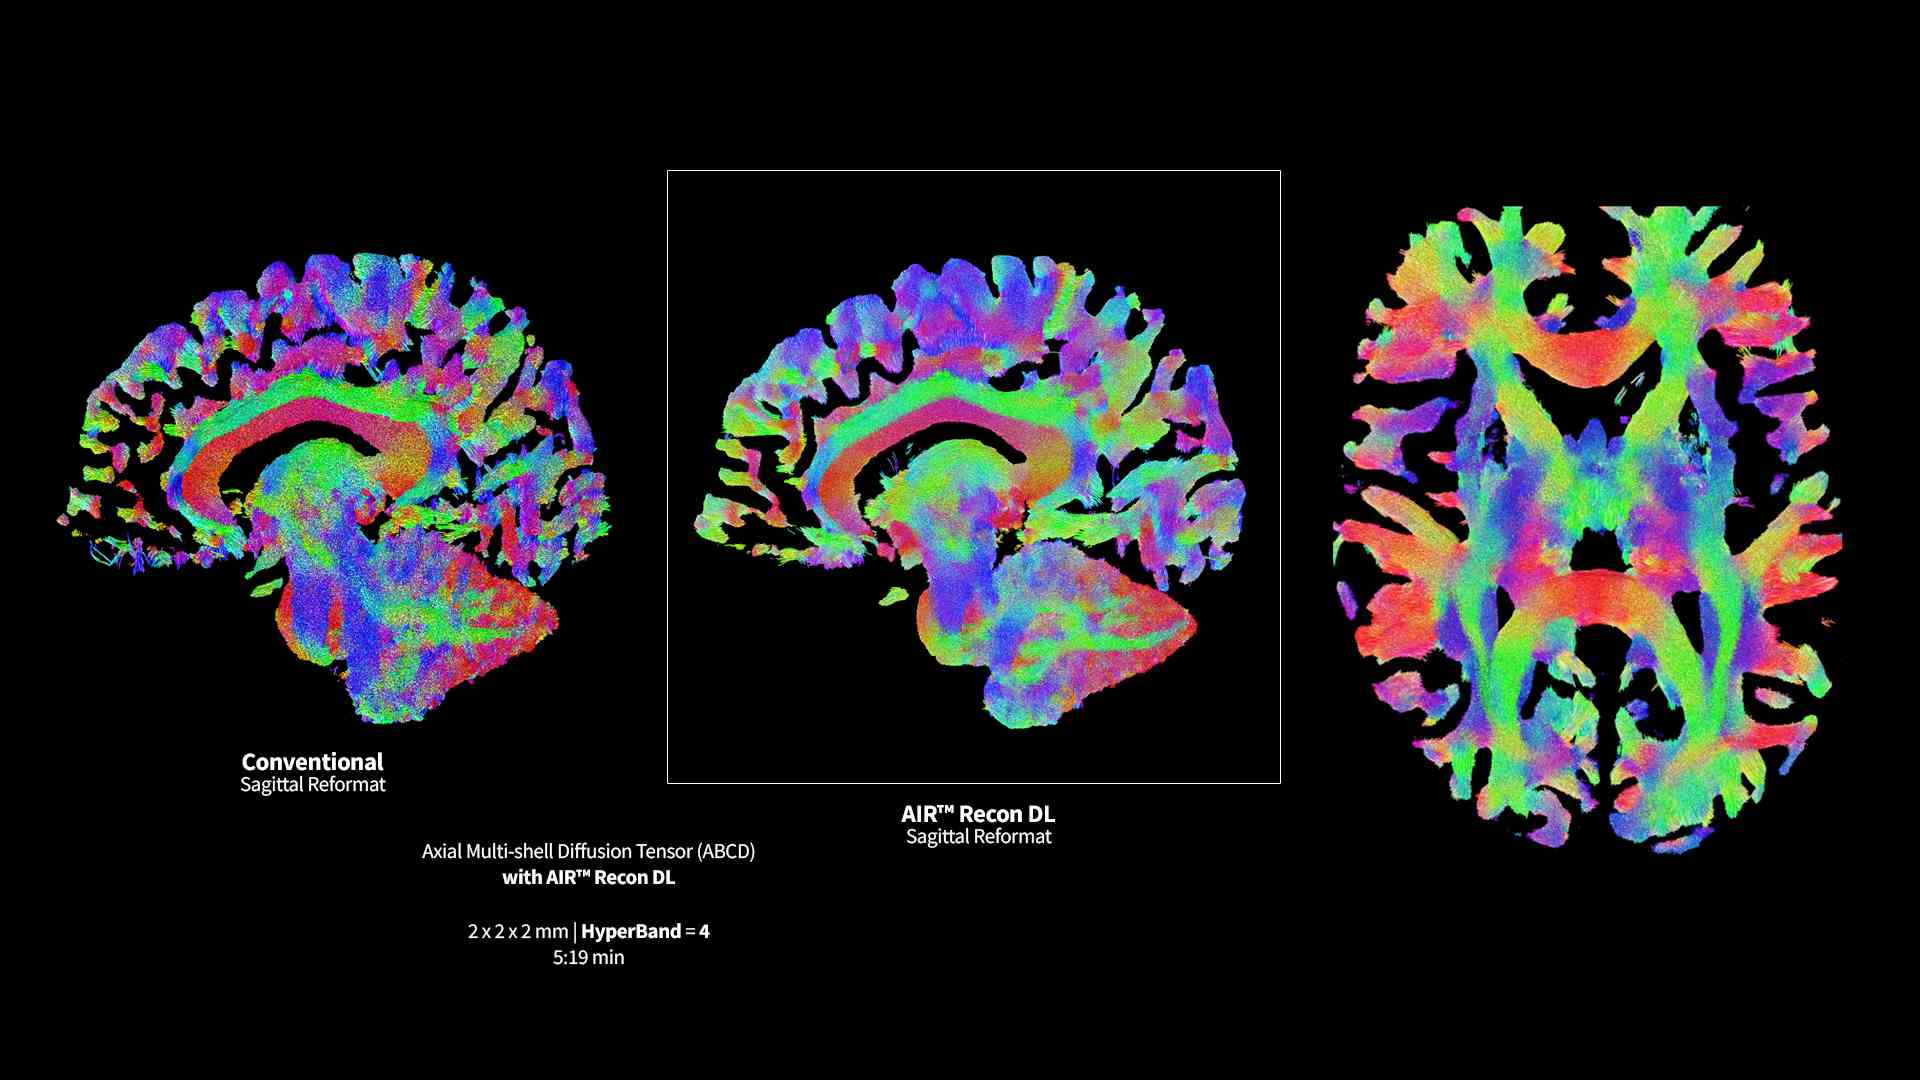

​SIGNA™ Premier supports the most demanding applications, such as Connectome-type studies that require Ultra-short TE diffusion imaging and high-resolution resting state fMRI. While it is a pioneering MRI system for cutting-edge research, it offers all the features needed to deliver routine clinical throughput. This includes delivering high end diagnostic image quality while ensuring the highest level of patient comfort.​

A powerful science tool with remarkable versatility

SIGNA™ Premier exemplifies many powerful robust attributes that makes it an exceptional MR for academic institutions. Alongside the SuperG gradients, which are proficient in executing the Human Connectome Protocol (HCP), the system has impeccable fMRI stability, a high RF-channel count with AIR™ Coils and a suite of deep learning applications.

Pin-sharp image quality and exceptional speed with AIR™ Recon DL and Sonic™ DL​

Experience pin-sharp precision and remarkable speed with a 3T SIGNA™ Premier MRI scanner, coupled with AIR™ Recon DL and Sonic™ DL.